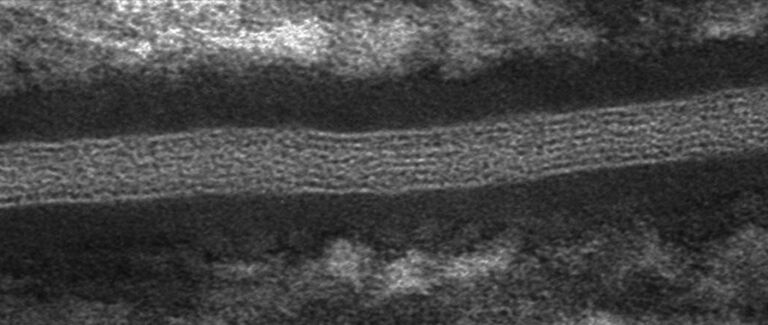

Microscopy Services setzt das patentierte Analyseverfahren Lipbarvis® (Lipid Barrier Visualisation, LBV) ein, um die epidermale Hautbarriere direkt ohne invasive Probenahmen untersuchen zu können.